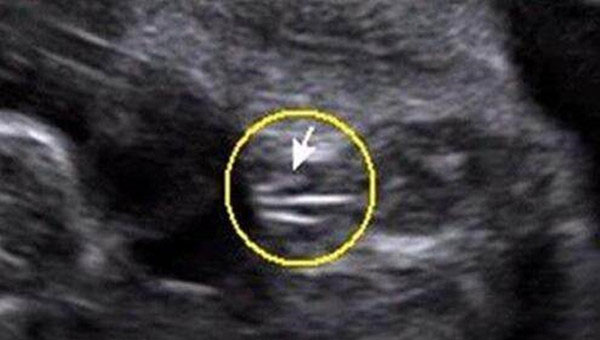

女宝宝从b超图中看到的影像,两腿中间有“三条白线”标志,这是女孩的外生殖器特征,也就是女宝宝的小阴唇。